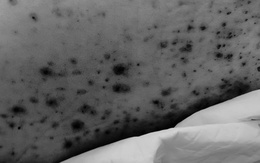

Một nam bệnh nhân 30 tuổi phải nhập viện điều trị tích cực vì biến chứng nặng của bệnh thủy đậu. Các bác sĩ cảnh báo thủy đậu không đơn giản như nhiều người vẫn lầm tưởng, bệnh có thể gây biến chứng nặng nề, thậm chí tử vong.

TP.HCM: Mắc thủy đậu, nhiều người trẻ gặp biến chứng nặng

Bệnh viện Bệnh nhiệt đới (TP.HCM) tiếp nhận điều trị nhiều trường hợp mắc thủy đậu nặng có biến chứng trên cơ địa trẻ khỏe, không bệnh nền.